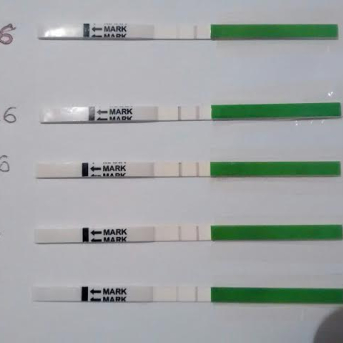

O teste de ovulação basicamente detecta um hormônio em abundância que faz o folículo romper e o óvulo sair para as trompas. O LH, hormônio luteinizante, em seus picos são capturados pelos anticorpos e reagentes existentes na tira de teste e fazem com que a linha de teste fique mais escura ou da mesma cor que a linha de controle. Caso a linha fique clara, então é sinal que o pico hormonal ainda não ocorreu.

A mulher que quer engravidar e usa o teste de ovulação para auxiliar, pode ter sucesso em grande maioria dos casos, pois ela saberia exatamente dentro de quanto tempo ocorrerá a ovulação, normalmente um prazo de 12 a 48 horas dependendo da intensidade da linha do teste.

O teste deve ser feito a partir do primeiro dia do período fértil, ou em mulheres desreguladas, assim que o muco ovulatório ou sintomas forem notados. Aliás, o muco é um forte indicio do inicio do período fértil. Ele tem duração aproximadamente de sete dias e pode ter o dia mais fértil por volta do quarto dia. Para mulheres que praticam o método da temperatura basal, o melhor dia de iniciar os testes seria no primeiro dia da queda da temperatura, pois o estrogênio provoca esta queda e sempre será sinal de que a ovulação está próxima. O melhor horário para fazer o teste seria à tarde, pois os hormônios estariam em um patamar equilibrado. Por volta das 16, 17 horas é um momento excelente!

O teste de farmácia complementa todos esses métodos de detecção. Os testes vendidos no Brasil têm cerca de cinco tiras e podem ser feitos durante todo o período fértil. Caso o teste não positive durante os dias que forem feitos, a mulher deve continuar a fazer mesmo que necessite de mais um kit de cinco testes. No entanto na grande maioria das vezes o teste chega a pegar o pico de LH sem maiores problemas. Esses episódios são isolados devido a ciclos com ovulação tardia.